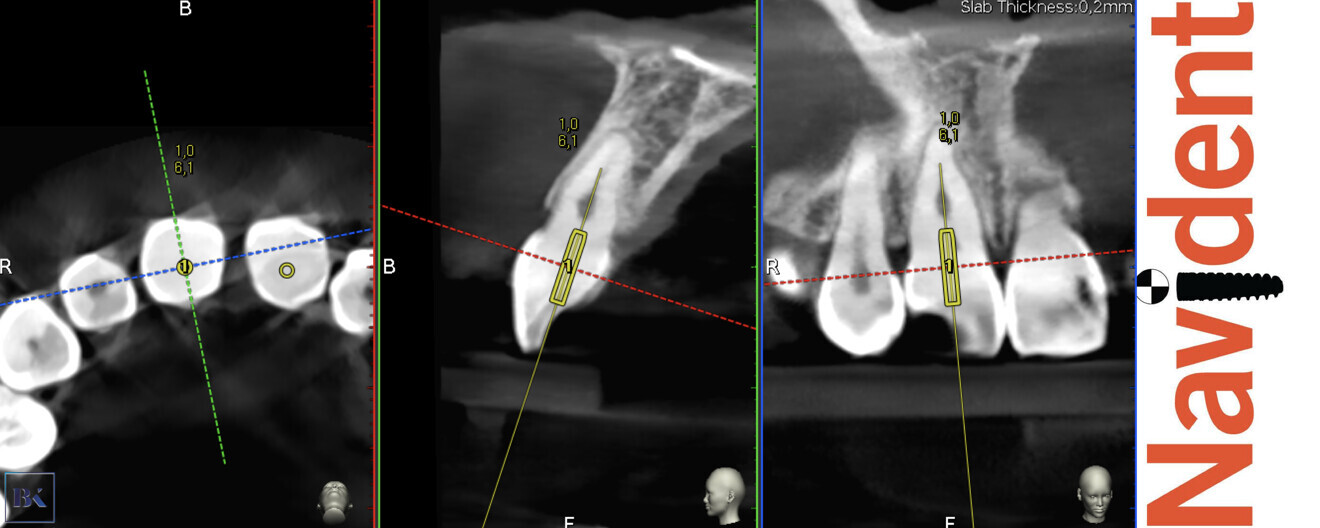

Before the treatment, the CBCT scan was uploaded to the software and the virtual guide was planned (Figs. 16 & 17). All the registration and calibration procedures were performed in the same manner as the previous case.

Figs. 16a–c: Planning of the virtual guide for the right incisor. The axis and depth of the preparation are shown.

Figs. 17a–c: Planning of the virtual guide for the left incisor. The axis and depth of the preparation are shown.